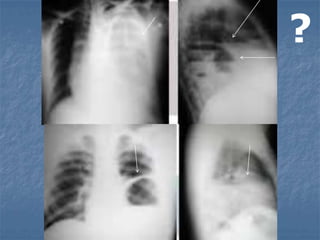

?

Cianosis craneofacial

Edema facial

Petequias

Aspecto moribundo

Inconciencia

Confusión

Hematuria

Hemotímpano

Epistaxis

ASFIXIA TRAUMÁTICA

Lesiones severas cerradas o por aplastamiento del

tórax y abdomen.

Aumenta la presión intratorácica y fuerza la sangre

al lado derecho del corazón, a las venas torácicas

superiores y del cuello.

La presión es transmitida a capilares del cerebro,

cabeza y cuello.

Distensión brusca de sangre estancada.

   Cianosis de cara y cuello.

   Edema y hemorragia de las

conjuntivas.

Manejo

Reconocer la entidad.

Mantener vía aérea

permeable.

Cuidado de lesiones

asociadas.

? Cianosis craneofacial Edema facial Petequias Aspectomoribundo Inconciencia Confusión Hematuria Hemotímpano Epistaxis

ASFIXIA TRAUMÁTICA Lesiones severascerradas o por aplastamiento del tórax y abdomen. Aumenta la presión intratorácica y fuerza la sangre al lado derecho del corazón, a las venas torácicas superiores y del cuello. La presión es transmitida a capilares del cerebro, cabeza y cuello. Distensión brusca de sangre estancada.

• 84.

Cianosis de cara y cuello.  Edema y hemorragia de las conjuntivas. Manejo Reconocer la entidad. Mantener vía aérea permeable. Cuidado de lesiones asociadas.